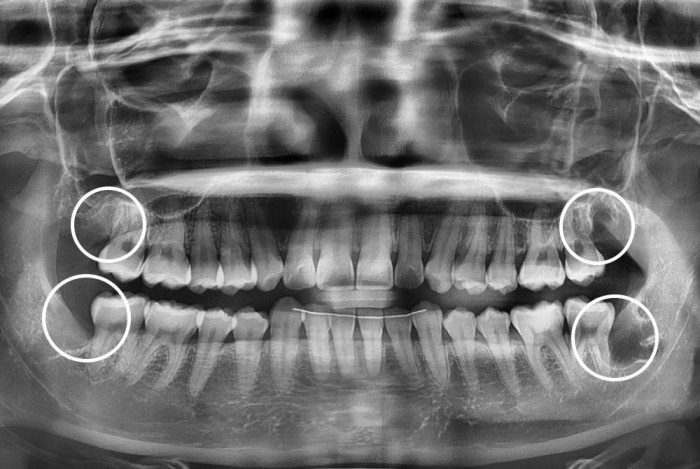

[사랑니] 사랑니

치료전 : 2025-10-11